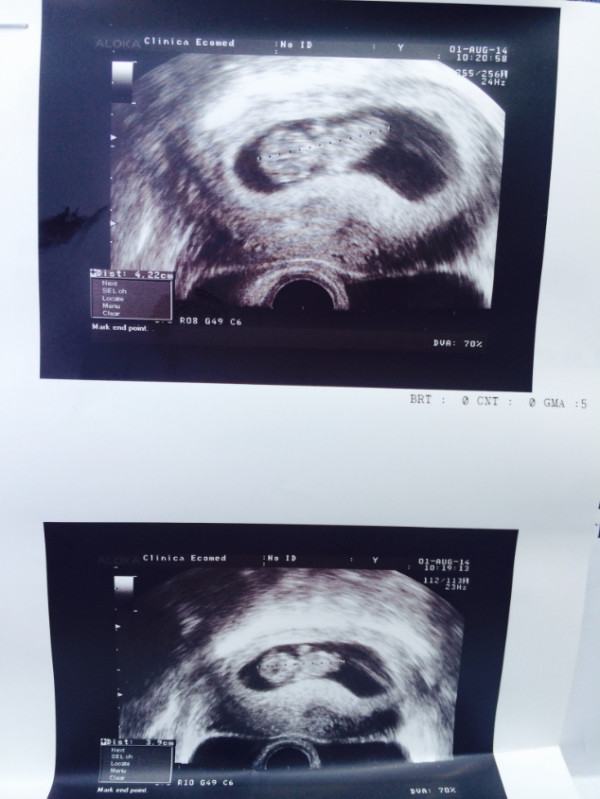

Совет! При проведении ультразвукового исследования могут быть измерены копчиково-теменные размеры плода, на 11 неделе беременности этот показатель составляет около 5 см. Но поскольку рост и развитие ребенка на этом этапе происходит стремительно, то уже через пару недель размеры вашего малыша увеличатся вдвое.

В первый раз рекомендуется проходить скрининг в период с 11 по 16 неделю. Причем врачи рекомендуют пройти это обследование, пока не началась 12 неделя беременности. Дело в том, что в это время хорошо видна воротниковая зона плода, а измерение этой части тела позволяет своевременно выявить наличие риска развития у плода синдрома Дауна.

Будущие мамы должны понимать, что при проведении УЗИ на 11 неделе беременности диагноз не ставят. Проведение скрининга позволяет определить степень риска. То есть, если будут получены результаты, не соответствующие норам, то будущей маме порекомендуют пройти дополнительные экспертные УЗИ и проконсультироваться у врача-генетика.

На сроке одиннадцати недель проводится первый пренатальный скрининг, который направлен на определение пороков развития. Производится ультразвуковое и биохимическое исследование. Первый скрининг направлен не только на выявление пороков развития. Данное обследование позволяет узнать состояние хориона, рост и степень развития плода, точный срок беременности и другие подробности.

Примерно к одиннадцати неделям ваш ребенок официально становится плодом от эмбриона.У вашего ребенка развиваются отчетливые черты лица и гениталии, а сканирование за одиннадцать недель дает захватывающее представление о том, как ваш ребенок растет внутри вас. Сканирование, выполняемое на одиннадцатой неделе, также имеет важное медицинское значение для исключения любых аномалий, синдромов или пороков развития.

Цель 11-недельного ультразвукового исследования

Сканирование беременности в первом триместре всегда особенное, так как оно дает представление о развивающемся ребенке. Сканирование на 11-й неделе дает вам возможность впервые увидеть, как выглядит ваш ребенок.Это также самая ранняя стадия, на которой врач может обнаружить у ребенка определенные аномалии. У сканирования на 11-й неделе много разных целей. Вот несколько причин, по которым нельзя пропустить 11-недельное сканирование.

- Во время 11-недельного сканирования плод проверяется на хромосомные аномалии, такие как синдром Дауна. Результаты сканирования оцениваются вместе с результатами анализа крови для постановки диагноза.

- Проверяют положение и размер плаценты.

- Оценивается количество околоплодных вод.

- Плотность затылочной кости (NT), измеряемая как полупрозрачное пространство в ткани под шеей плода, используется в качестве фактора оценки риска синдрома. Прозрачность затылочной кости также используется в качестве ориентира для исключения любых врожденных сердечных заболеваний.

- Многоплодная беременность, если таковая имеется, четко видна во время этого сканирования. Близнецы обычно видны на этой стадии как два четко отдельных гестационных мешочка.

- Произведена общая оценка состояния здоровья беременной.

- Гестационный возраст ребенка проверяется по росту плода.